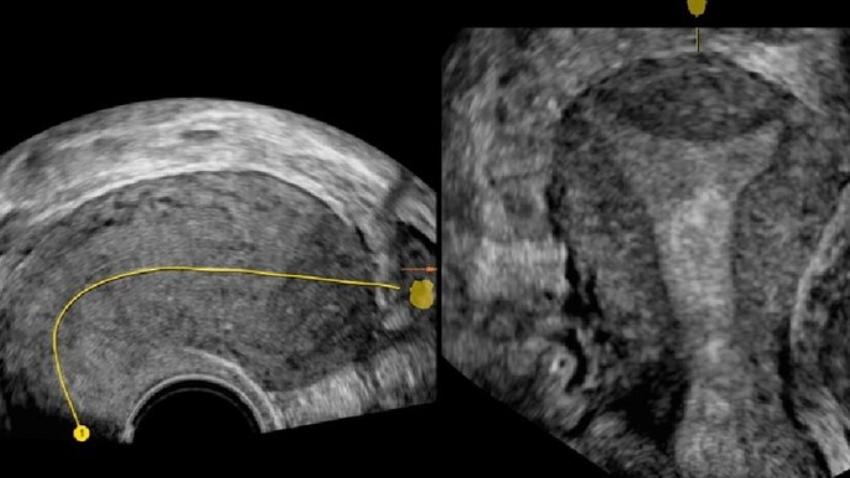

HSG (Hysterosalpingogram ) in rohini delhi

HSG (Hysterosalpingogram ) in rohini delhi HSG test near me C-8/193 sec 8 rohini delhi 9811552...